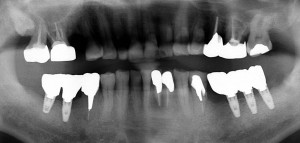

現在の状態 左下(写真では右下)5番部は骨の状態が悪かったので、遠心よりに埋入したためカンチレバーになってしまった 右上5番歯根破折で抜歯

現在の状態 左下(写真では右下)5番部は骨の状態が悪かったので、遠心よりに埋入したためカンチレバーになってしまった 右上5番歯根破折で抜歯

次々起こる歯根破折